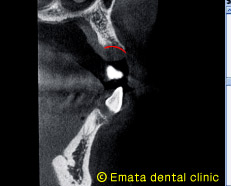

上記レントゲン画像のAのラインでのCTの断面です。外側の骨(赤線)が残っていることが確認できました。 |